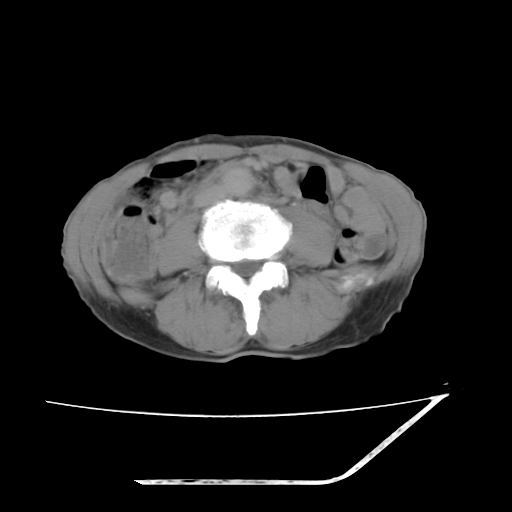

平扫

增强

考虑右肾盂癌,肾动脉受侵,右肾功能减退,右肾盂输尿管积水,管壁增厚,考虑种植转移,应该把下面扫完的

支持右侧肾盂癌伴肾静脉瘤栓形成可能性大,右肾结石.肝右叶后段低密度影,不除外转移.

右肾盂旁ca并肾静脉瘤栓形成/肾功能降低。

右肾结石。

右肾盂癌,肾动脉受侵,右肾盂输尿管积水,管壁增厚,考虑种植转移

支持 右侧肾盂癌伴肾静脉瘤栓形成可能性大,右肾结石;肝右叶后段低密度影,不除外转移。

1.右侧肾盂癌伴肾盂积水。

2.肾脏功能减退,原因有:(1)肾动脉受侵。(2)肾静脉受侵(3)肾积水,等。本例,肾动脉显影较好,但受压明显;肾静脉无明显显示,受压或静脉癌栓,下腔静脉腔内未见明显充盈缺损。

3.右侧上段输尿管扩张,原因:(1)积水所致;(2)种植。